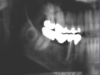

What is the radiographical finding?

Odontogenic

Keratocyst

OKC